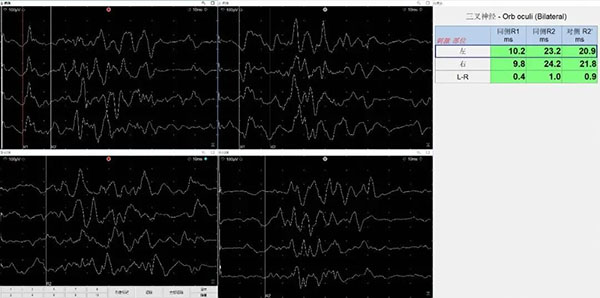

瞬目反射(Blink Reflex)

瞬目反射是评估面神经与三叉神经反射弧功能的重要检查, 常用于定位脑干、面神经核 及三叉神经感觉通路病变:在眶上缘或鼻梁处刺激三叉神经(V1分支)记录双侧眼轮匝肌的反应潜伏期与波形(R1、R2)潜伏期延迟或波形缺失提示脑干反射弧通路损害,对面肌痉挛、面神经病变、桥小脑角病变等的功能评估具有重要价值。